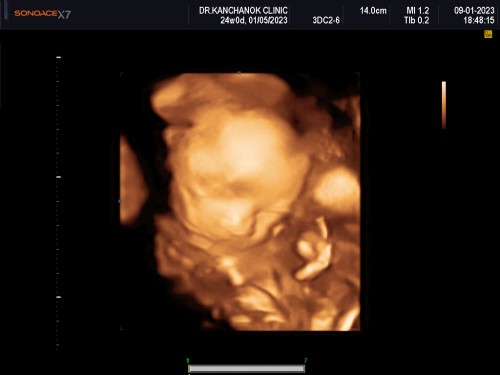

เด็ก24w. ช่วยตั้งชื่อทีค่าาาา

#ท้องแรกคะ น้อง24w เห่อน้องมากๆ น้องเป็นผู้ชาย ช่วยตั้งชื่อหน่อยได้มั้ยคะ คิดไม่ออกเลยจริงๆ 🥰